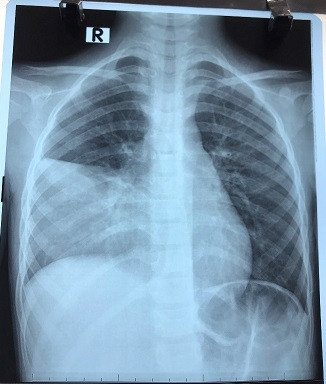

Chuyên gia phân tích về phòng bệnh viêm phổi do vi khuẩn Mycoplasma ảnh 2Hình ảnh phim chụp của một bệnh nhân mắc viêm phổi do Mycoplasma pneumoniae. (Ảnh: PV/Vietnam+)